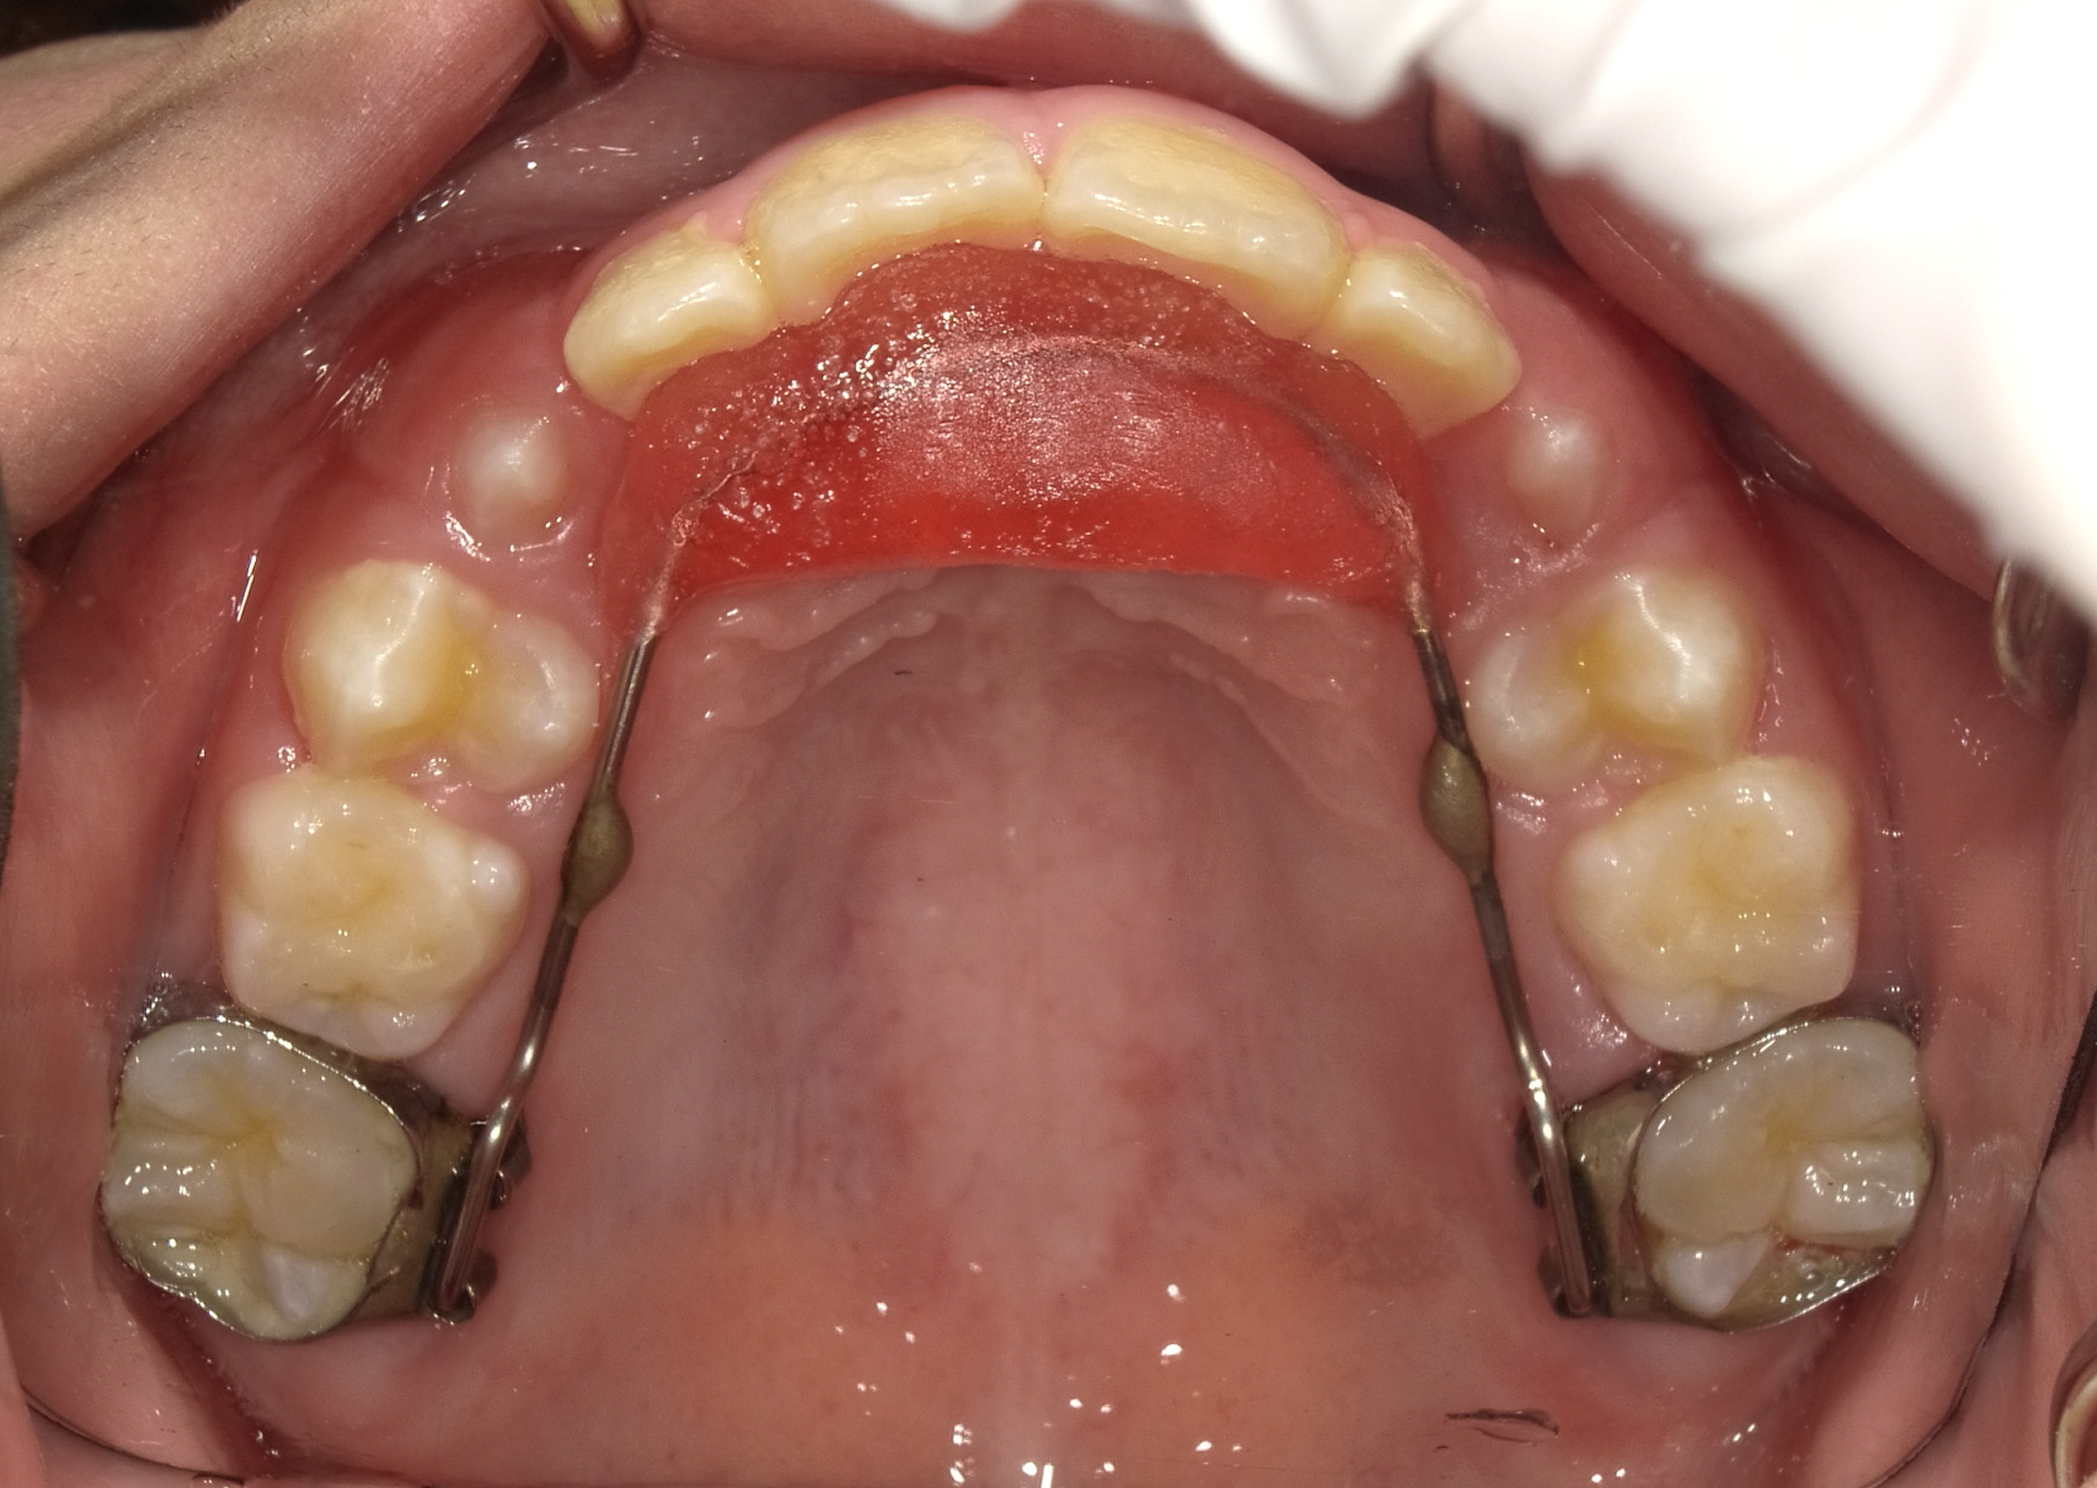

まずは拡大床という装置を使い、凸凹の改善を目指します。

1期矯正の経過

時間はかかりますが、だいぶ凸凹が改善してきました。しかしまだ正面か見ると下の歯が見えません。

今回は上の歯が出過ぎているというより、下の顎は引っ込みすぎていると診断し、下顎を前に誘導する装置を使用します。

装置使用前後の比較

前歯に若干の凸凹はありますが、あとは2期治療で簡単に改善可能です。